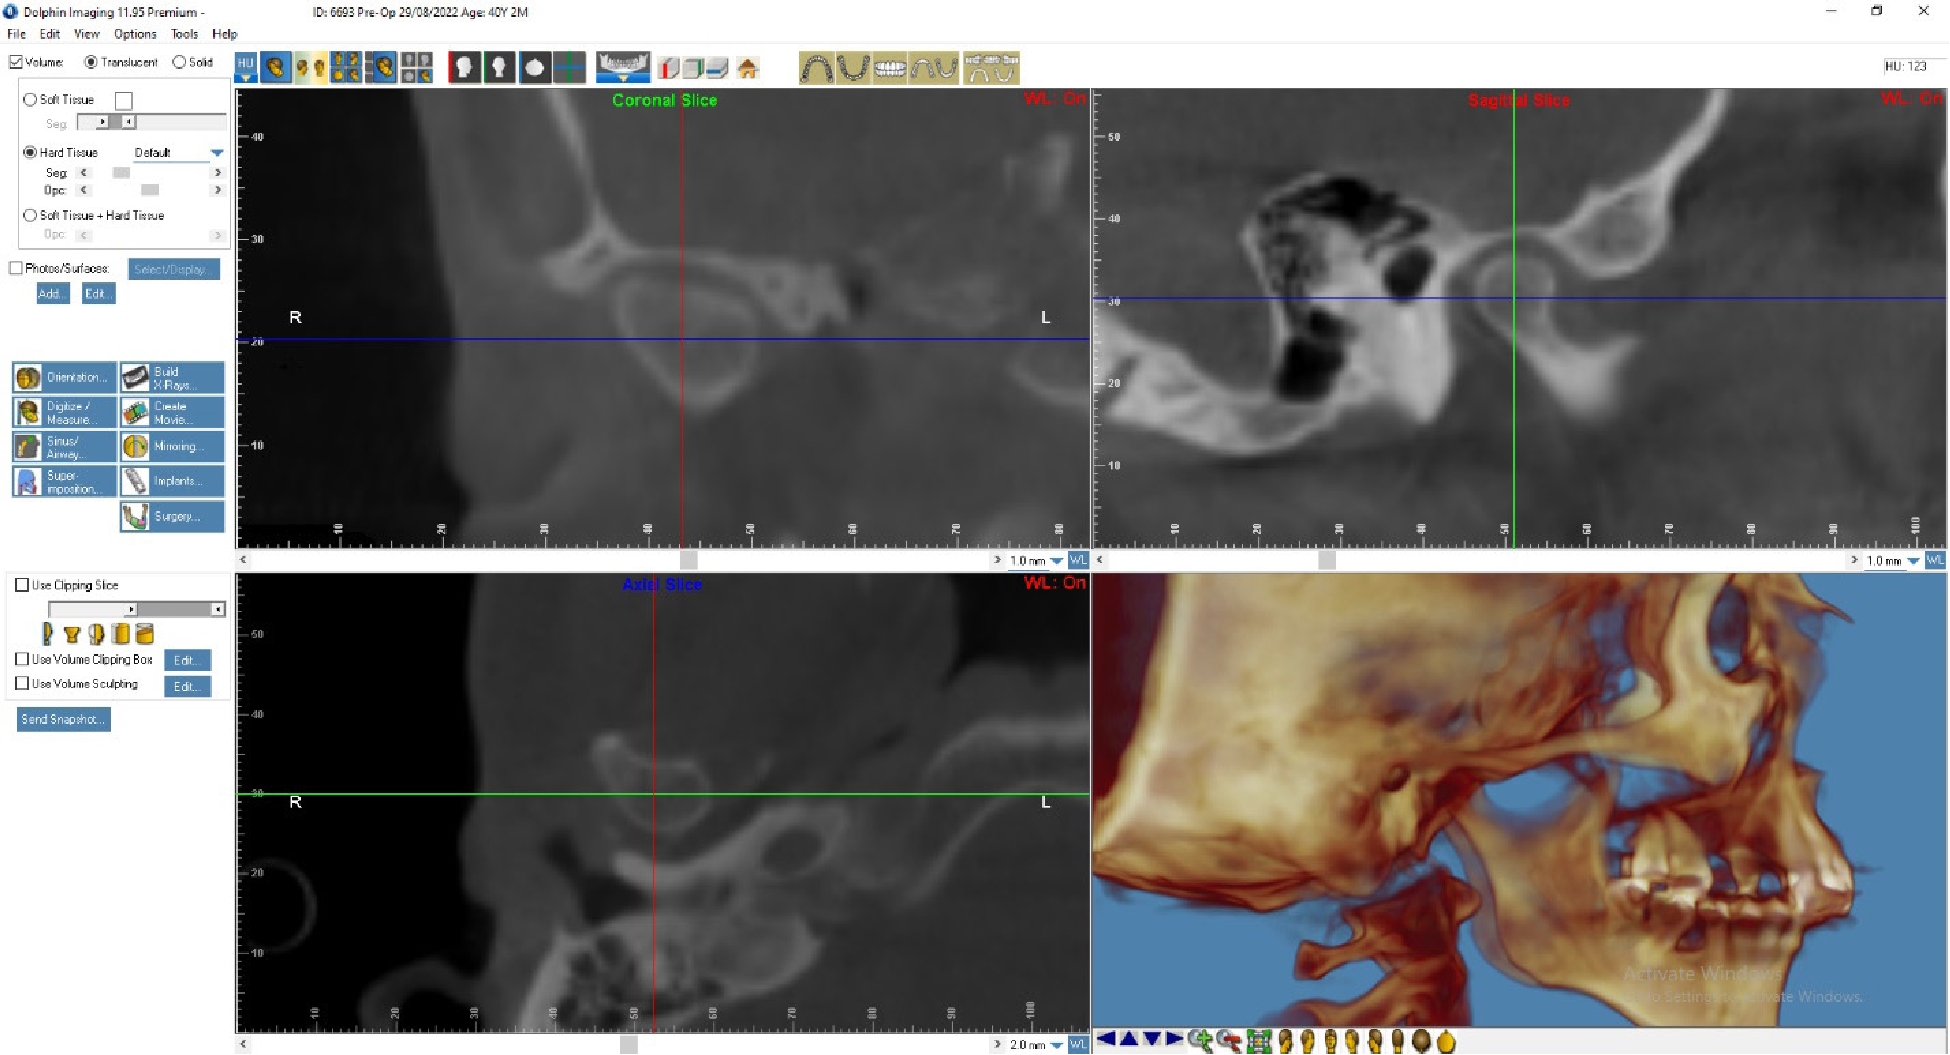

На основании КТ с использованием лицензионной программы Dolphin Imaging 11.95 Premium определяли цефалометрические параметры черепа и анатомические изменения в ВНЧС. Для интерпретации результатов МРТ использовали Radiant Dicom Viewer.

Лечение: Пациенту Д. была выполнена окклюзиограмма, на основании которой были устранены супраконтакты методом избирательного пришлифовывания зубов. Также было выполнено лечение сплинт-терапией для восстановления работы височно-челюстного сустава. Фиксирована брекет-система на зубы нижней челюсти (рис. 3, 4).

По данным МРТ ВНЧС спустя 2 года после начала лечения отмечается устранение вентро-латеральной дислокации суставного диска в положении привычной окклюзии. Также устранен синовит, увеличился объем движения в суставе (рис. 5). Как видно из рис. 4 и 5, по данным КТ ВНЧС спустя 2 года после начала лечения отмечается ремоделирование головки нижней челюсти. Клинически увеличилось открывание рта до 38 мм.

Рис. 5. Пациент Д., 40 лет. КТ ВНЧС спустя 2 года после начала лечения